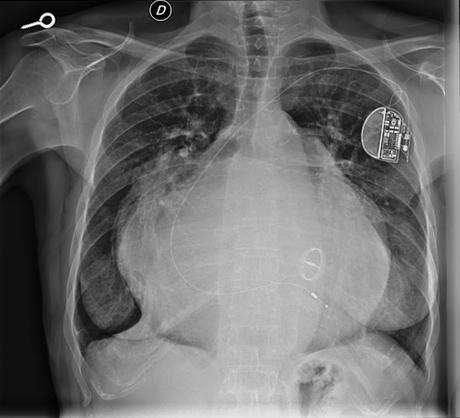

La persona radiografiada tiene una cardiomegalia, esto es, un corazón grande. Y créanme si les digo que en verdad lo es: porque es el más grande que yo, personalmente, he visto en mi consulta y en toda mi vida.

Obviamente, la "grandeza" de este corazón se debe al padecimiento, ya desde la infancia, de varias enfermedades. En la imagen la mancha blanca central corresponde al corazón, en el que podemos ver que se han implantado una válvula y un marcapasos...